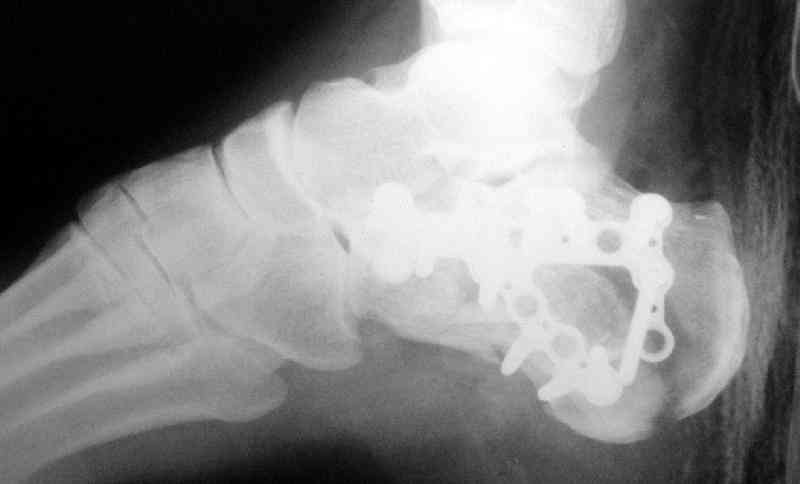

Пяточной пластиной

С уважением, А.Семенистый.

ГКБ № 13, Москва.

Открытый и закрытый способы лечения.